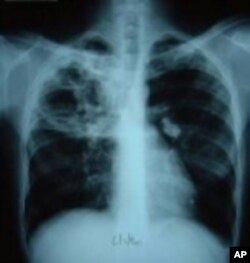

Wata kwayar halittar cuta wadda ke kama huhu, ita ce take haddasa tarin fuka ko TB. Idan har aka kama da wuri, ana iya warkar da wannan cuta da kwayoyin kashe cuta. Haka kuma ana iya yin rigakafinta da allurar rigakafi. Amma duk da haka, miliyoyin mutane su na kamuwa da tarin fuka su na kuma mutuwa a kowace shekara, akasari a kasashen Afirka da Asiya.